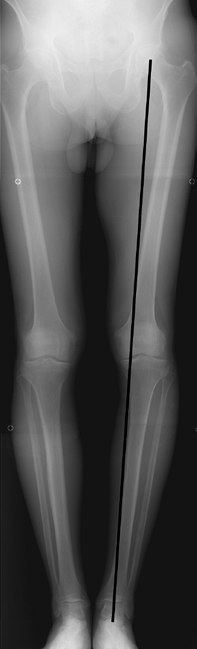

intersection of lines drawn parallel to the long axes of the femur and

tibia and is typically between five and seven degrees of valgus. In

most patients, the standing AP view allows for adequate assessment of

tibiofemoral alignment in the coronal plane. However, patients with

pre-existing congenital, posttraumatic, or postsurgical deformities of

the femur or tibia require an AP long-leg hip to ankle radiograph for

accurate assessment of the anatomic axis (Fig. 17-4).

The mechanical weight-bearing axis of the knee, illustrated by a

straight line drawn from the center of the femoral head to the center

of the ankle joint, can also be determined on the long-leg radiograph.

A line passing through the middle third of the proximal tibia

represents a neutral mechanical axis, whereas lines passing through the

medial third and lateral third represent varus and valgus mechanical

axes, respectively.

Figure 17-4

Anteroposterior long-leg hip-to-ankle radiograph. The mechanical axis of the limb is determined by a line between the center of the femoral head and the center of the ankle. |